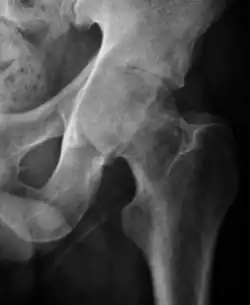

Radiological signs of transient osteoporosis of the hip include localized osteoporosis of the femoral head and neck (Figure 8). Nevertheless, final diagnosis has to be made with MRI to differentiate it from avascular necrosis and from insufficiency or stress fractures of the femoral head or neck. In case of AVN, radiographs can only demonstrate delayed or advanced signs. Staging according to Ficat classification ranges between normal appearance (stage I), slight increased density in the femoral head (stage II), subchondral collapse of the femoral head with or without “crescent” sign (stage III), and advanced collapse with secondary osteoarthritis (stage IV). In the case of stress or insufficiency fractures X-ray sensitivity has been proven to be much lower than MRI, which is currently the gold standard.[1]

Figure 8:

-

X-ray of a patient with transient osteoporosis of the left hip showing osteoporosis.[1] -

Coronal stir imaging in transient osteoporosis, showing diffuse edema.[1] -

Scintigraphy (A), sagittal T1 (B), and coronal PD fat sat of a patient with a subchondral fracture of the femoral head with convex shape to the articular surface.[1] -

Coronal T1 of a patient with avascular necrosis of the femoral head.[1]